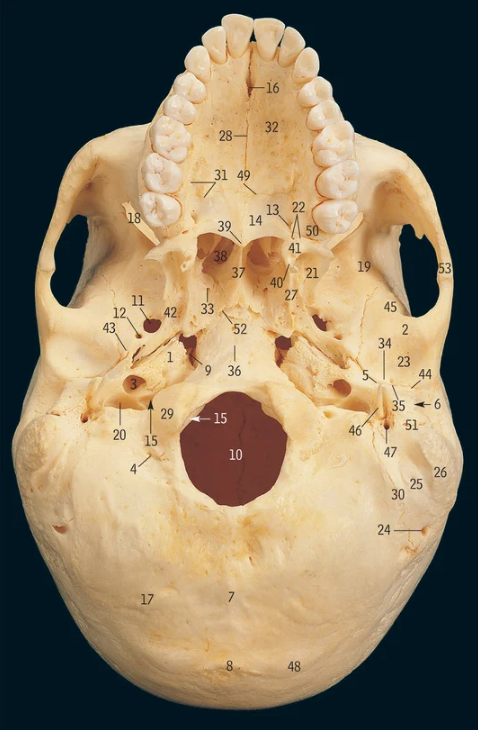

Lateral pterygoid plate

13

Medial pterygoid plate

19

Supra-orbital notch

29

Occipital condyle

48

Superior nuchal line

Which part of the ethmoid bone does the olfactory nerve exit

Cribiform plate

Which part of the ethmoid bone does the falx cerebri attach

Crista galli

Which part of the frontal bone does the supra-orbital nerve travel through

What cranial nerves travel through the superior orbital fissure

CN III/3, IV/4, V1/ophthalmic, VI/6

What travels through the hypoglossal canal

Hypoglossal nerve

What travels through the formen magnum

Spinal cord, accessory nerve

What muscles attach to the superior nuchal line

Occipitalis and trapezius

37

Zygomatic process of temporal bone

What muscle attaches to the zygomatic process of the temporal bone

18

Mastoid processÂ

Petrous part of temporal bone

28

Internal auditory meatus

9

Mandibular fossa

3

Carotid canal

46

Styloid process

47

Stylomastoid foramen